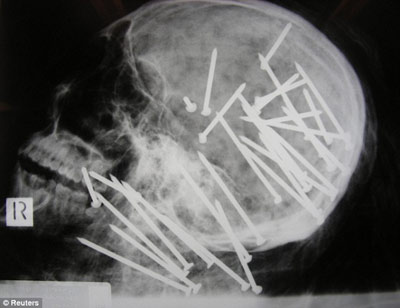

X光顯示,劉晨(音譯)頭部和頸部被釘有30枚鋼釘

據(jù)報道,該男子名叫劉晨(音譯),于2000年移民澳大利亞墨爾本市,4年后搬往悉尼。2008年11月,劉晨的男性友人向悉尼警方報案,稱其已經(jīng)失蹤一段時間,警方遂展開調查。兩周后,兩名在悉尼喬治河上劃船的男孩發(fā)現(xiàn)了劉晨已經(jīng)高度腐爛的浮尸。警方稱,當時劉晨被一條毯子緊裹著,四肢被電線捆得結結實實,警方將尸體交與法醫(yī)進行X光檢查后驚異地在他頭部和頸部發(fā)現(xiàn)了30枚鋼釘。

負責本案的警官馬克·紐漢表示:“尸檢結果顯示,兇手用一種無繩氣動式射釘槍對著死者的頭部和頸部開了30槍,這種標準式射釘槍哪都可以買到?!毕つ峋窘芊颉へ惱姿垢5赂嬖V記者:“這起謀殺案令所有的警察震驚不已,在我36年的辦案生涯中,還從來沒見過性質如此惡劣的兇案……就是因為這起謀殺案是如此的殘忍,所以我們希望公眾能夠為警方提供更多的破案線索?!?/p>